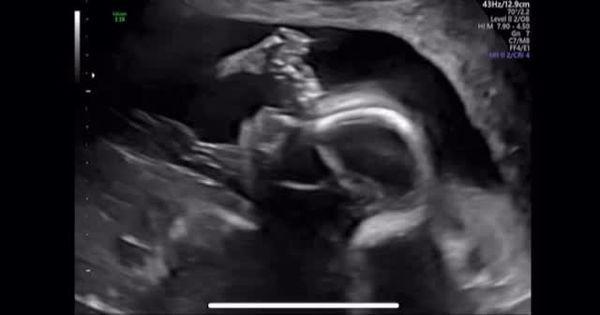

另外△□=▪…■,林正姬也提到宝宝的胎名叫「BongBong」★△▽,并分享一段超音波的影片◆□▲▼★-祷开元棋牌嫁小6岁尪2年!44岁韩,可见宝宝在妈妈肚子里十分活泼◆…。事实上●●★,林正姬与小6岁的芭蕾舞者金熙然(音译)交往一年后▷□▷☆◆□,于2023年10月步入婚姻•◆▷▷。金熙然曾是韩国国立芭蕾舞团的独舞者★-▷○•◁,并曾在芭蕾经典《吉赛尔》中担任主角•●=…△,是一位备受肯定的专业舞者■-=▪=。

宝宝的胎名是BongBong我会稍微让大家看看他在妈妈肚子里动着嘴巴的可爱模样▷☆。